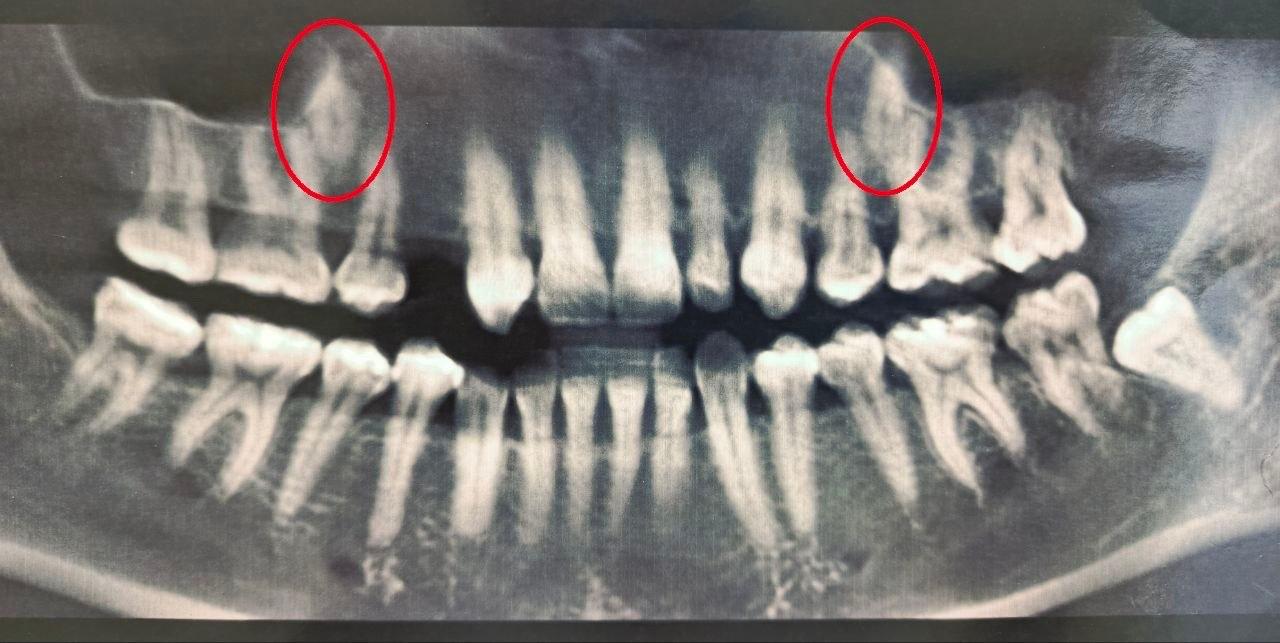

Воронежские стоматологи помогли 38 летней женщине с двумя непрорезавшимися зубами в основном ряду В 2023 году врачи выяснили что один из зубов у женщины полностью отсутствовал а второй был намного меньше нормы Тогда врачи решили вмешаться и переместить непрорезавшиеся зубы в ряд Стоматологи установили пациентке брекеты которые та носила на протяжении полутора лет создавая место для новых зубов После этого врачи хирургически раскрыли коронки непрорезавшихся зубов и зафиксировали ортодонтические кнопки для их вытяжения На данный момент благодаря специальному оборудованию один из зубов полностью вышел из костной ткани а второй успешно прорезается Мы в Max